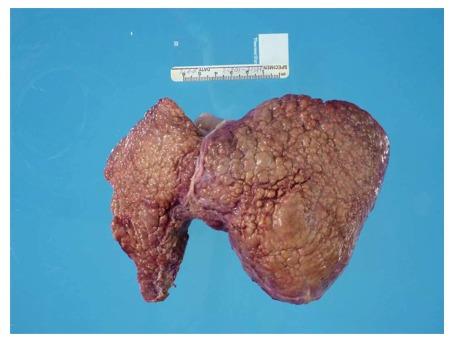

Hereditary tyrosinemia type 1 (HT-1) is a metabolic disorder caused by a defect in tyrosine degradation. Without treatment, symptoms of hepatomegaly, renal tubular dysfunction, growth failure, neurologic crises resembling porphyrias, rickets and possible hepatocellular carcinoma can develop. The use of 2-(2-nitro-4-trifluoromethylbenzoyl)-1,3-cyclohexanedione and early diagnosis through newborn screening initiatives have resulted in a sharp decline in morbidity and mortality associated with this disease. We present a case report of a 7-year-old patient with HT-1 who was born prior to the addition of tyrosinemia to the newborn screening in her birth area. At her time of diagnosis, the patient had developed many of the symptoms associated with her disease, including chronic kidney disease, rickets, and myopathy that left her non-ambulatory. During her initial evaluation, she was also noted to have hepatocellular carcinoma. With cadaveric liver transplantation and nutritional support, her symptoms all either resolved or stabilized. Her case illustrates the severity of the disease if left untreated, the need for vigilance in populations who do not routinely receive newborn screens, and the markedly improved outcomes in patients following transplant.

1型遗传性酪氨酸血症(HT - 1)是一种由酪氨酸降解缺陷引起的代谢紊乱疾病。若不进行治疗,可出现肝肿大、肾小管功能障碍、生长发育迟缓、类似卟啉病的神经危机、佝偻病以及可能的肝细胞癌等症状。使用2 -(2 - 硝基 - 4 - 三氟甲基苯甲酰基)- 1,3 - 环己二酮以及通过新生儿筛查项目进行早期诊断,已使该疾病相关的发病率和死亡率大幅下降。我们报告一例7岁HT - 1患者的病例,该患者出生时其出生地尚未将酪氨酸血症纳入新生儿筛查项目。在诊断时,患者已出现许多与该疾病相关的症状,包括慢性肾病、佝偻病和肌病,导致她无法行走。在初次评估时,还发现她患有肝细胞癌。通过尸体肝移植和营养支持,她的症状全部得到缓解或稳定。她的病例说明了若不治疗该疾病的严重性、对未常规接受新生儿筛查人群保持警惕的必要性,以及移植后患者的预后显著改善。